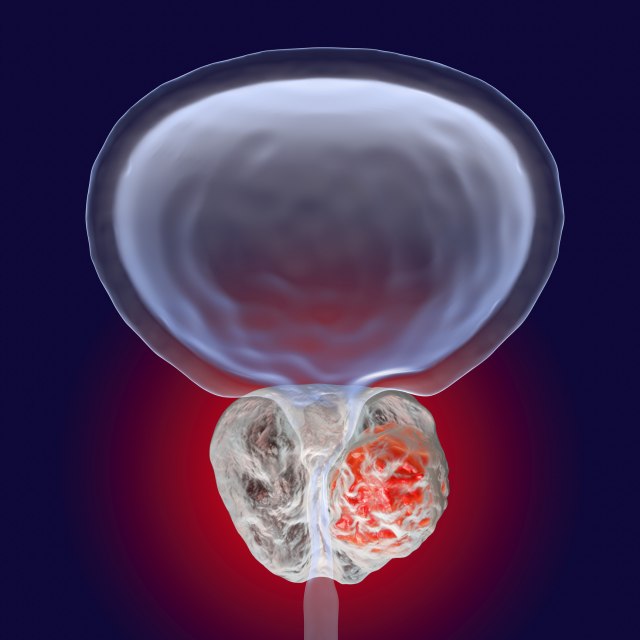

Naučnici su identifikovali 63 nove genetske mutacije povezane sa tim karcinomom, koje su kombinovali sa više od 100 genetskih varijanti DNK, za koje se već zna da dovode do te bolesti. Test bi mogao koštati oko 40 evra, piše

Jedan odsto muškaraca nosi rizične genetske varijacije zbog kojih imaju veći rizik obolevanja, navodi studija. DNK mutacije se pretežno javljaju u ćelijama koje regulišu komunikaciju između imunološkog sistema i drugih delova organizma.

Naučnici sa londonskog Instituta za istraživanje raka (ICR - The Institute of Cancer Researc) planiraju da ustanove može li ispitivanje uzoraka DNK iz pljuvačke muškarca da prepozna rizične osobe. Za sada, muškarci rade testove krvi koji procenjuju marker, specifični antigen (PSA) čiji nivo raste ako se pojavi karcinom. Rezultati mogu dati iskrivljenu sliku zbog intenzivnog vežbanja, urinarnih infekcija, pušenja i određenih lekova.

"Ako znamo koliko je verovatno da muškarac dobije karcinom prostate, naš sledeći korak je da vidimo da li možemo da tu informaciju iskoristimo za prevenciju bolesti", kaže profesor Ros Eles iz ICR.

Rak prostate je, u poslednje vreme, po smrtnosti preskočio karcinom dojke. Razvija se uglavnom vrlo sporo, i dugi niz godina ne mora da bude bilo kakvih simptoma da ga muškarac ima. Ako se dijagnostifikuje u kasnijoj fazi, kad se već proširio, postaje terminalan. Pacijenti koji imaju pozitivan rezultat rade biopsiju, koja isto tako ne predstavlja potpuni dokaz, prenosi

Lekari se bore kako da razlikuju da li se radi o agresivnom ili o manje ozbiljnom tumoru. Teško je odlučiti i o načinu lečenja. Naučnici ne znaju šta izaziva karcinom prostate, ali su godine, debljina i nedostatak kretanja poznati rizici.